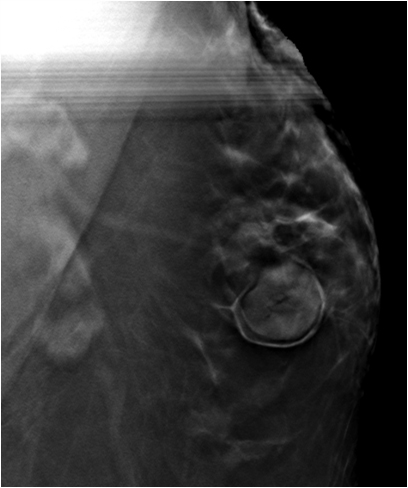

BI-RADS 2 Benign Pseudohamartoma appearance of a Chronic Galactocele within the accessory breast tissue

Galactocele is a milk-filled retention cyst caused by the obstruction of the lactiferous duct. It is the most common benign breast mass in women who are or who recently stopped lactating. Clinically, it manifests as one or multiple painless palpable masses On mammography, galactocele can exhibit various imaging features depending on the proportion of fat and protein in the individual's breast milk. When completely radiolucent with a relatively high fat content, it is known as pseudolipoma. A cystic mass with a fat-fluid level is a diagnostic indicator of a galactocele, with the fat content above and the water content remaining at the bottom. Alternatively, when the high viscosity of breast milk does not allow the separation of the fat and water contents, a galactocele can resemble a hamartoma; this condition is known as pseudohamartoma

Mammography Accessory breast tissue in the left axillary region. Fat containing oval mass with circumscribed margins and a thin capsule around it. Additional left axillary tail view done . Ultrasound Oval mass with circumscribed margin,complex solid and cystic with no vascularity on color doppler.